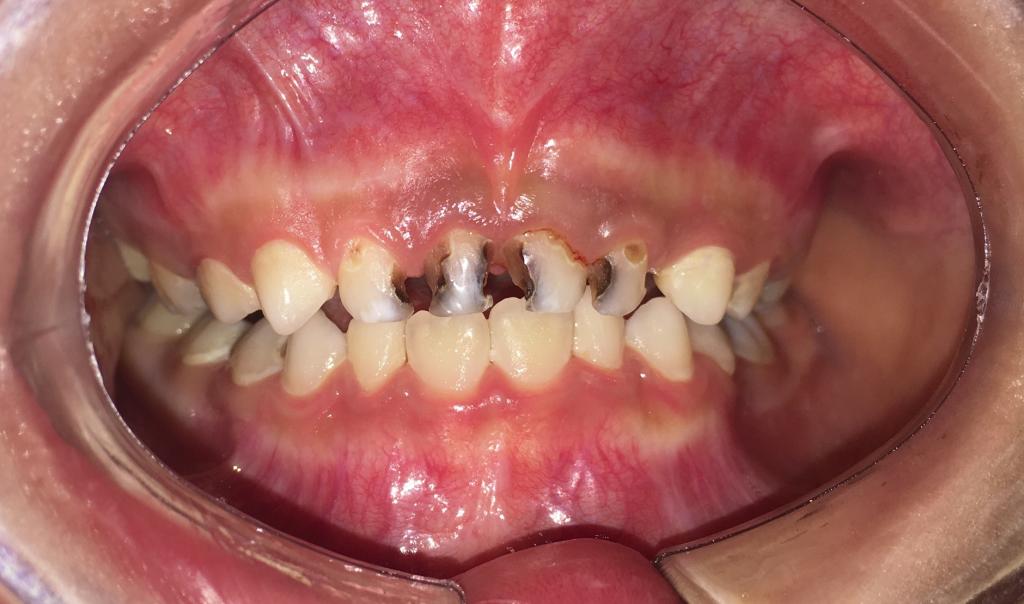

吃糖的最大坏处就是容易导致蛀牙,糖摄入过多,加上不注意口腔卫生致使食物残渣残留,糖会被细菌分解发酵,产生酸性物质,侵蚀牙齿,使牙齿遭到破坏。预防宝宝蛀牙,糖是头号大敌。